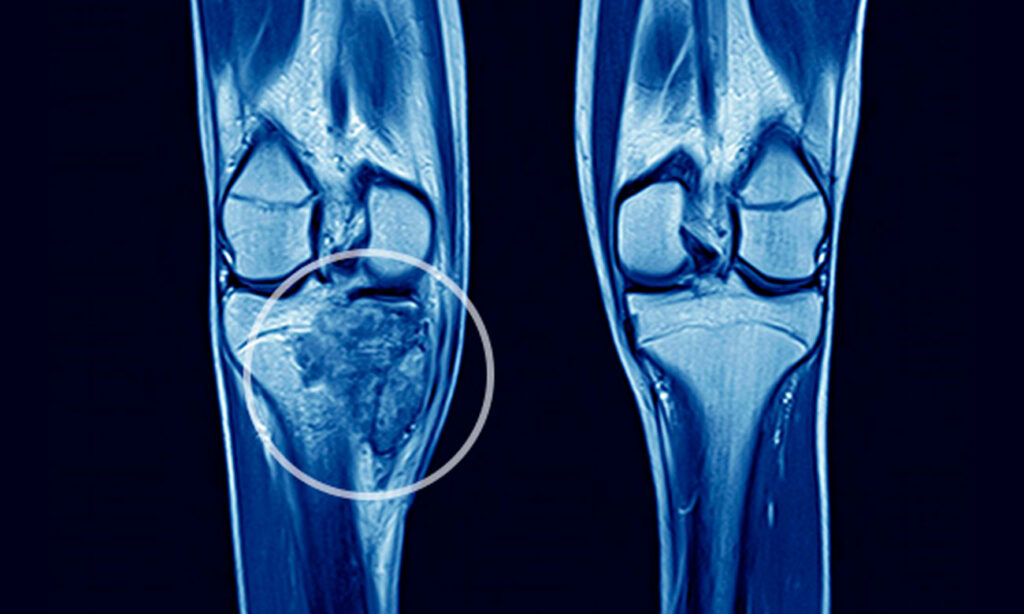

Os tumores ósseos podem ser classificados como benignos ou malignos, e sua origem está relacionada ao crescimento anormal das células que compõem os ossos e a cartilagem. Quando células ósseas escapam do controle normal de proliferação, elas podem formar tumores. Alguns desses tumores são benignos, ou seja, não se espalham para outras partes do corpo, mas outros podem ser malignos, apresentando riscos à saúde.

Por outro lado, o osteossarcoma é um tipo de tumor ósseo maligno e, infelizmente, muito mais grave. O osteossarcoma é caracterizado pela presença de osteoblastos pleomórficos (células de morfologia irregular e variada) e uma alta taxa de mitose, o que indica a divisão rápida e descontrolada dessas células. Este tipo de tumor ósseo ocorre com mais frequência em adolescentes e adultos jovens, e as áreas mais comumente afetadas incluem a extremidade inferior do fêmur e as extremidades superiores da tíbia e do úmero.Embora o osteossarcoma seja raro, ele é um dos tipos de câncer ósseo mais comuns e requer tratamento imediato, geralmente envolvendo uma combinação de cirurgia e quimioterapia.